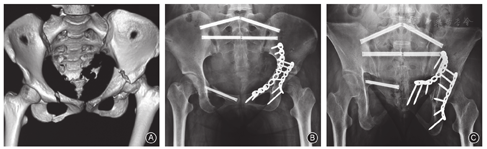

骶髂螺钉可沿钉道轴线均匀分散载荷,是临床公认的治疗骨盆后环损伤的首选方式。骶髂螺钉主要适用于:(1)骶髂关节复合体脱位或骨折脱位;(2)骶骨DenisⅠ、Ⅱ型及部分Ⅲ型骨折;(3)Tile B、C型骨盆损伤;(4)陈旧性骶髂关节脱位或骶骨骨折的截骨矫形;(5)污染相对轻微的骨盆后环开放性损伤;(6)多发伤伴骨盆后环损伤的早期处理;(7)协同髂腰内固定治疗(图3)。

Schildhauer等[23]应用切开复位髂腰三角固定治疗骶骨DenisⅠ、Ⅱ区骨折或骨盆骨折合并腰骶结合部损伤等取得了满意疗效。

机器人辅助经皮髂腰三角固定(图4)的主要手术步骤:(1)俯卧位,常规CT扫描确认L5椎弓根形态。(2)规划螺钉位置。(3)经皮建立工作通道,机器人辅助椎弓根钉置入。(4)在髂后上棘处做长约3 cm的皮肤切口,经LC-Ⅱ通道后方置入髂骨钉(长度100~130 mm),其入点在髂后上棘下缘,出点分别指向髋臼上缘或髂前下棘。术中保持钉尾内聚且向头侧倾斜并居于髂骨内外板之间。(5)连接钉棒系统,在髂嵴切口处利用辅助工具作适度纵向撑开以纠正或改善骶骨骨折的垂直移位。(6)在同一体位下完成骶髂螺钉固定。(7)当骨折残存移位影响骶髂螺钉通道时,可改行骨盆后方钢板微创固定。骨折闭合复位是术中面临的主要难题,目前常用的解决方案为[24,25,26]:(1)术前持续大重量骨牵引复位;(2)术中通过改变患者体位协助复位;(3)利用Schans钉、顶棒等并结合手法复位;(4)髂腰内固定器械复位。

髂腰三角固定存在一定的理论缺陷和治疗争议。这种跨越L5S1脊柱功能单位的固定方式,在腰骶椎间微动的作用下可能发生钉棒松动或断裂,从而影响骨折愈合;术中单边过度撑开复位可能导致L5S1间盘在轴向上受力不均,造成脊柱侧凸;另外局部生物力学环境的改变可能加速其解剖结构的退变[25,26]。为了弥补髂腰三角固定的不足,有学者提出了骶髂三角固定的概念[24,25,26],即利用S1椎弓根螺钉与髂骨钉连接并辅以骶髂螺钉固定。其优点是手术创伤小、操作简单、切口并发症少、不影响腰骶活动等。如果术中发现S1椎体被椎弓根螺钉过度占用而无法行骶髂螺钉置入,可选择S2通道完成固定。这种更短节段的固定方式理论上具有可行性,但其力学强度仍有待研究证实。

经皮髂腰固定是在Galveston技术的基础上,由Käch和Trentz[27]于1994年首先提出且目前已得到多数学者的认同的固定方式[25,26,27]。髂腰固定由椎弓根、髂骨钉棒系统及其横联组成,其双平面支撑固定有一定的结构优势,类似于三维互锁内固定支架,可平衡骨盆后环的异常应力,在一定程度上起到复位和固定的双重作用。该方法可重建腰骶部的解剖序列和整体稳定,减少骨折部位的应力传导。其工作原理是模拟脊柱的长度、角度、提拉及去旋转复位过程。术中虽难以完全纠正骶骨横行骨折的侧方移位或成角畸形,但术后骨盆入射角明显改善,为脊柱矢状面平衡提供了解剖基础。另外,也在一定程度上避免了腰椎过度前凸的发生[28]。